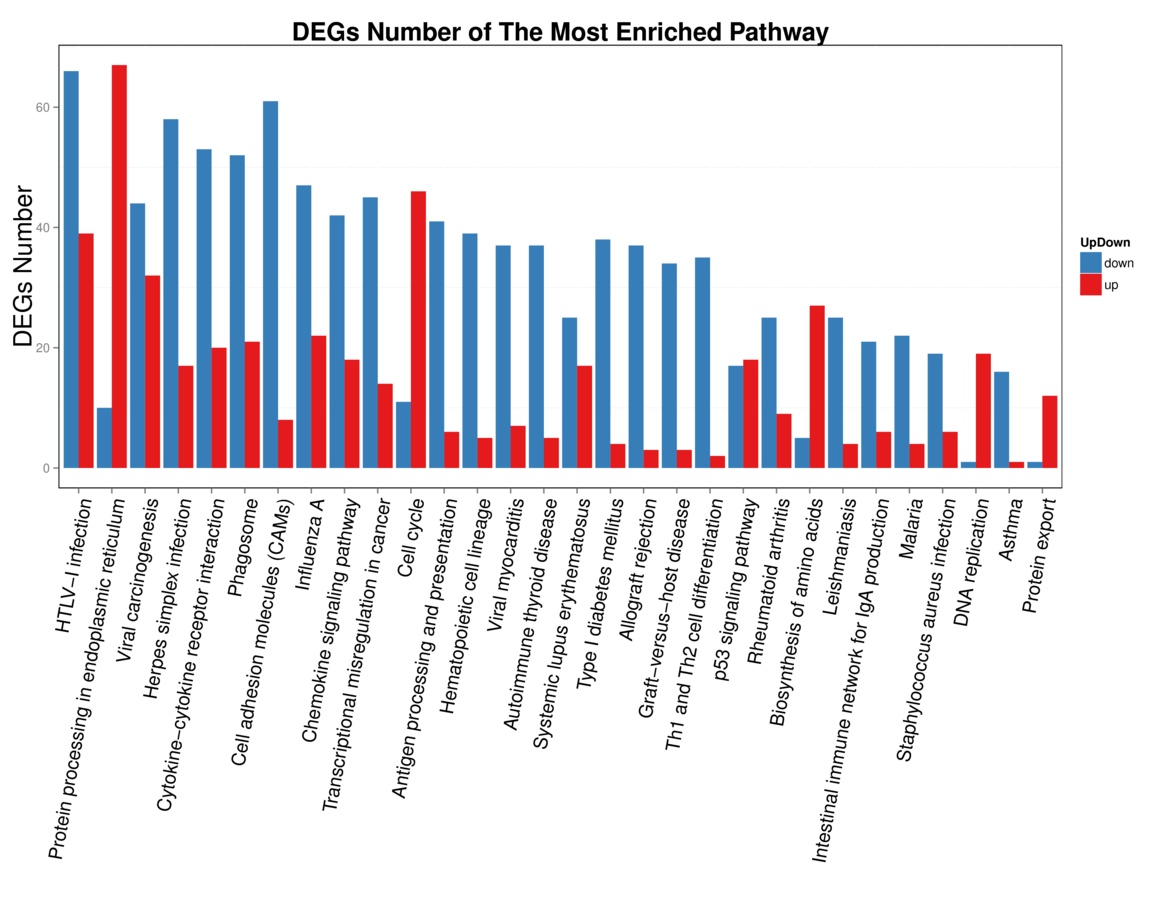

2 结果48 h各组病理结果,对照组脾组织结构正常(见图 1A )。脓毒症组脾组织见白髓结构破坏,红白髓交界模糊,多量组织细胞浸润,红髓充血(见图 1B)。差异mRNA的Volcano-plot分布图(见图 2)。相比于对照组,24 h时脓毒症组脾组织mRNA表达上调的有1 030个,下调的有935个[5];48 h组表达上调的有1 354个,下调的有1 763个。差异mRNA的聚类情况(见图 3)。GO功能分类结果(见图 4)。脓毒症大鼠脾组织部分通路相关基因表达情况(见图 5、6):脓毒症大鼠24 h,48 h脾组织关于细胞因子及其受体相互作用通路相关基因的分布图(见图 7,图 8)。脓毒症大鼠24 h,48 h脾组织关于细胞凋亡相关通路的基因分布图(见图 9,图 10)。

| X轴:GO功能分类,Y轴:对应GO Term中的基因数。 图 5 脓毒症大鼠24 h组 |

| 图 6 脓毒症大鼠48 h组 |

早期过度炎症反应、晚期免疫抑制系脓毒症的重要机制之一[6-7]。脾脏为人体免疫器官,在血源性抗原出现时,负责启动免疫反应[9]。脓毒症时SIRS反应可引起脾功能障碍[10]。本研究发现脓毒症48 h大鼠脾组织白髓结构破坏,红白髓交界模糊,其结构改变可能影响其免疫功能。既往对脓毒症大鼠24 h采用基因芯片分析发现部分基因表达异常[11]。若能进一步研究其早晚期的相关基因表达变化也许对脓毒症脾功能障碍有进一步的诠释。本研究采用RNA-seq技术对脓毒症大鼠早晚期脾组织行mRNA检测,是既往研究的深入,发现脓毒症早期组脾组织基因上下调数远少于晚期组,如脓毒症24 h组脾组织mRNA上调数1 030个,下调数935个,而48 h组mRNA上调数1 354个,下调数1 763个,差异明显(见图 2),符合疾病的发展过程。从图 3看,脓毒症24 h、48 h部分区域从红色趋于变浅甚至变蓝,浅蓝趋于蓝色,直观的反应脓毒症时脾脏基因表达量变化情况。从GO功能分类结果(图 4)得知,cellular processes、Environmental informationProcessing、Genetic Information Processing、Human Diseases、Metabolism、Organismal Systems相关功能基因随时间发展出现差异表达数为上升趋势。进而我们对其分析发现,脓毒症早晚期脾mRNA出现变化主要涉及细胞因子与其受体相互作用、IL-17、T细胞受体、TH1、TH2细胞分化、TNF、Toll受体、凋亡等相关信号通路。研究显示,脓毒症晚期免疫抑制可能是脓毒症患者死亡的主要原因,免疫治疗可能是未来一大趋势[12-15]。本文拟从炎症反应与细胞凋亡相关通路来阐述脓毒症脾功能障碍的相关机制。